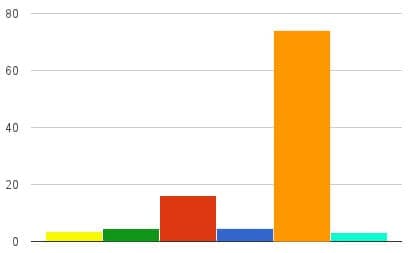

Die Effektivität wurde in unserer Forschungseinrichtung untersucht und bestätigt. Das Produkt unterging zahlreichen klinischen Tests mit Freiwilligen. Die Ergebnisse haben die hohe Effektivität von Exodermin bestätigt:

- Mycoloc

- Lamesyl

- Exoderil

- Loceryl

- Exodermin

- Mycosan